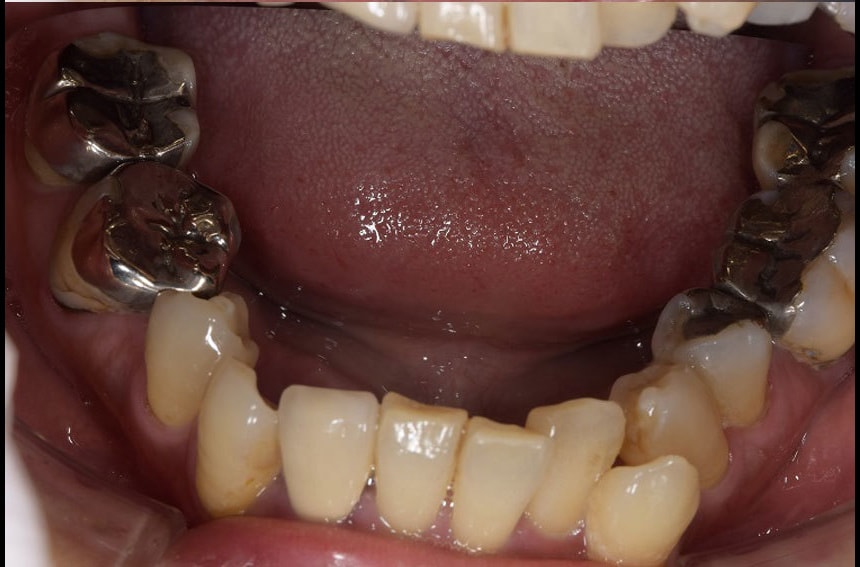

前歯の治療前後

上の歯の治療前後

下の歯の治療前後